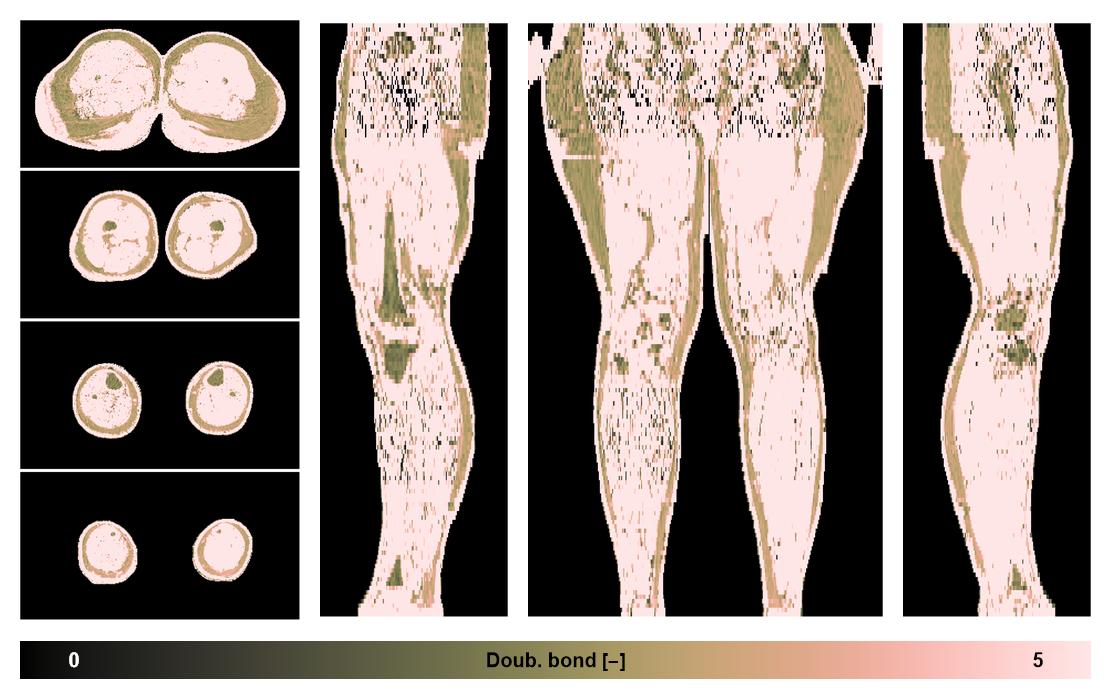

• Number of double bonds in subcutanious fat

Number of double bonds in subcutanious fat.